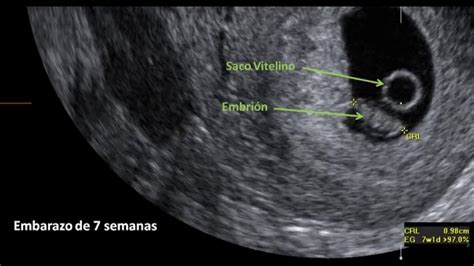

El saco gestacional aumenta de tamaño a medida que avanza el embarazo. Alrededor de las 5.5 semanas de gestación, la vesícula vitelina (también denominada saco vitelino) en desarrollo se vuelve visible. El embrión surge a partir de las 6 semanas de gestación, próximo a la vesícula vitelina, e inicialmente mide entre 1 y 2 mm de longitud.

La ecografía transvaginal muestra el saco gestacional, que puede identificarse ya con 2-3 mm de diámetro a las 2-3 semanas de embarazo (4-5 semanas desde la fecha de la última menstruación). La vesícula vitelina es la primera estructura que puede identificarse en el interior del saco gestacional. El saco vitelino crece a un ritmo de 1 mm por semana hasta alcanzar 6 mm en la semana 10 y disminuye a partir de entonces, no siendo visible ya a las 12-13 semanas.

Con 5 semanas de gestación, es posible observar por ecografía la vesícula vitelina dentro del saco gestacional, confirmando de esta manera que hay embrión y que la gestación es evolutiva. El embrión se observa como una estructura de unos 2-3 mm, junto al saco vitelino.